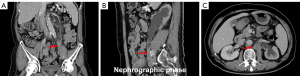

A urologic ultrasound examination revealed dilation in the upper left ureter, characterized by an internal diameter of approximately 1.60 cm. Additionally, a hypoechoic mass measuring 3.92 cm × 1.47 cm was observed 5.0 cm from the left renal hilum-ureteral junction (within the ureter), displaying a class I blood flow signal on color Doppler flow imaging (CDFI). Adjacent to the left renal hilum, an enlarged hypoechoic lymph node measuring about 2.33 cm in diameter was identified (Figure 1). Computed tomography urography (CTU) revealed a soft tissue density mass within the lumen of the left mid-ureter, appearing as a strip measuring approximately 1.20 cm at its widest point, with a measured area of involvement of about 4.10 cm. The CT attenuation values were 42 Hounsfield units (HU) in the plain phase, 73 HU in the corticomedullary phase, and 70 HU in the nephrographic phase, with enhancement scans displaying moderate enhancement. Both the ureter and the renal calyces above the lesion exhibited dilation and hydronephrosis, contributing to a reduction in both volume and perfusion of the left kidney. Adjacent to the abdominal aorta and left iliac vessels, multiple enlarged lymph nodes were evident (Figure 2).